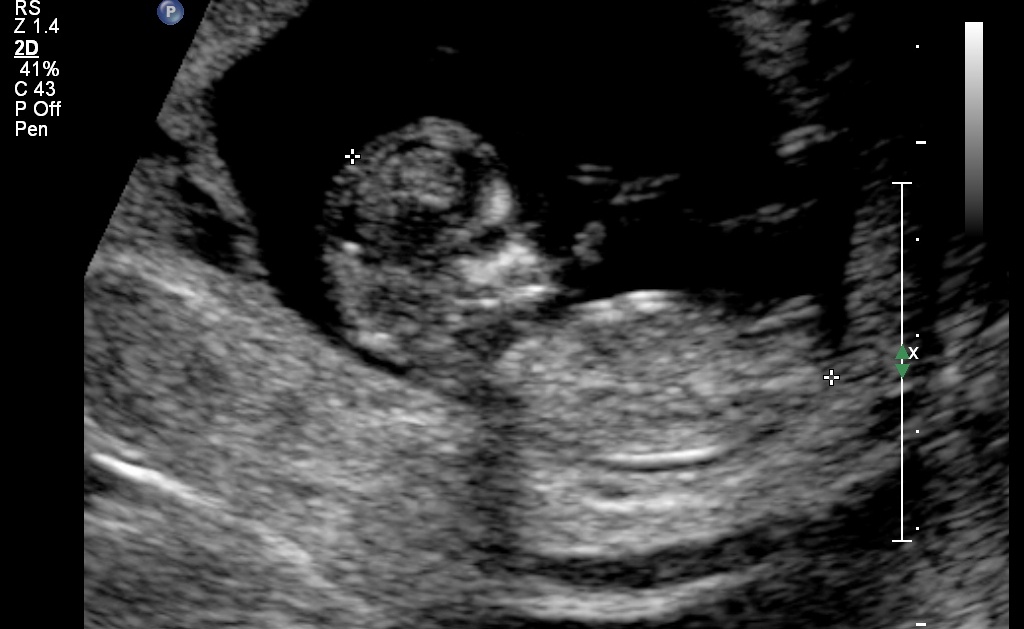

After 6 boys we are really hoping for a girl. Can any one please take a guess. :-)

Attachment 21856

Definitely looks girly :) excited for you!

looks girly!

I'm wondering if the 3rd pic is showing an angled boy nub ontop of the main white line?? I may lean boy on this one but hope its your girl for you!!!

Leaning pink

Looks girly- good luck!